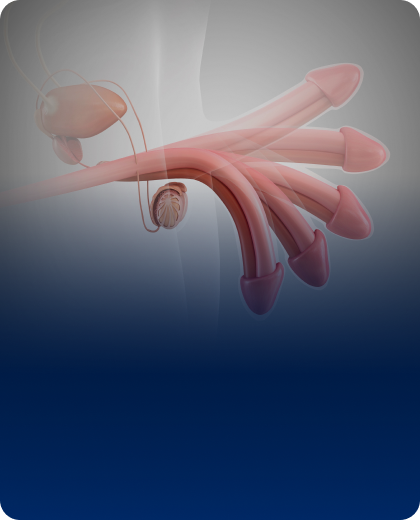

남성의 신체 구조는 해부학적으로도, 기능적으로도 특수성을 가지고 있습니다.

전립선 질환, 발기부전, 요로결석, 남성 확대술, 재건 수술까지.

하나의 증상이 배뇨 기능과 성기능을 동시에 흔들 수 있고, 단순 미용 수술이 기능 보존과 직결되기도 합니다.

단순한 크기 변화가 아닌 해부학적 구조를 고려한 확대 설계, 음경확대, 귀두확대, 길이연장, 실리콘 보형물 등 기능 보존을 기반으로 시술합니다.

함몰음경, 음경만곡증, 이물질 제거, 인공고환 삽입 등 구조 교정과 재건 중심의 수술로 외형 개선이 아닌 정상 구조 복원을 목표로 합니다.

약물 치료, 자가주사요법, 저강도 체외충격파, 보형물 수술까지. 기능 회복을 단계별로 설계하는 남성 기능 클리닉입니다.

전립선염, 전립선비대증, 결찰술·아이틴드·리줌 등 비절제 최소침습 치료를 중심으로. 배뇨 기능과 성기능의 균형을 설계합니다.